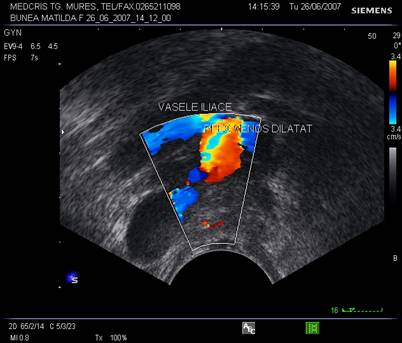

Fig. nr.396. La ecografia tranvaginala asociata cu Doppler , plexul venos dilatat se diferentiaza facil de un chist ovarian